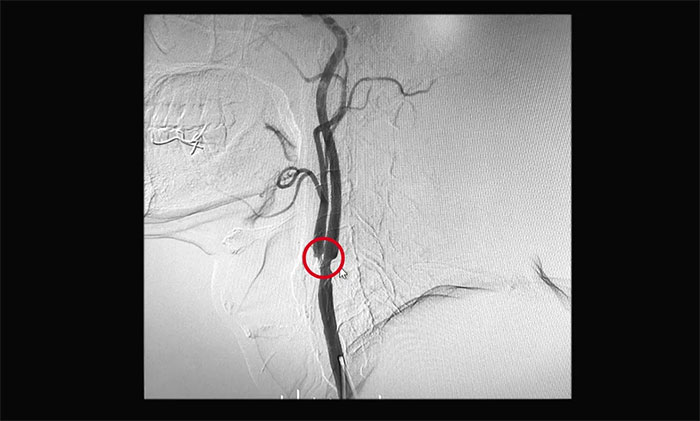

医院神经外科6A病区医生团队详细了解黄先生的病史,并进一步完善相关检查。行DSA脑血管造影检查后,显示患者左侧颈内动脉起始部狭窄约70%,左侧颈外动脉起始部狭窄约90%,属于重度狭窄,应考虑手术治疗。

▲ DSA检查示左侧颈动脉重度狭窄